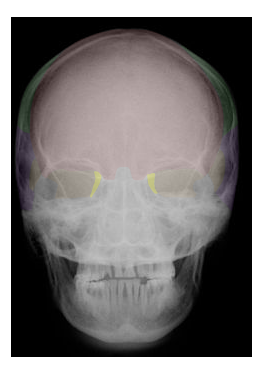

Cranial and Facial Bones

Students will use images and descriptions to reinforce their knowledge of the cranial and facial bones.

A | B |

| FRONTAL |

| SPHENOID |

in yellow,  | ETHMOID |

in green,  | PARIETAL |